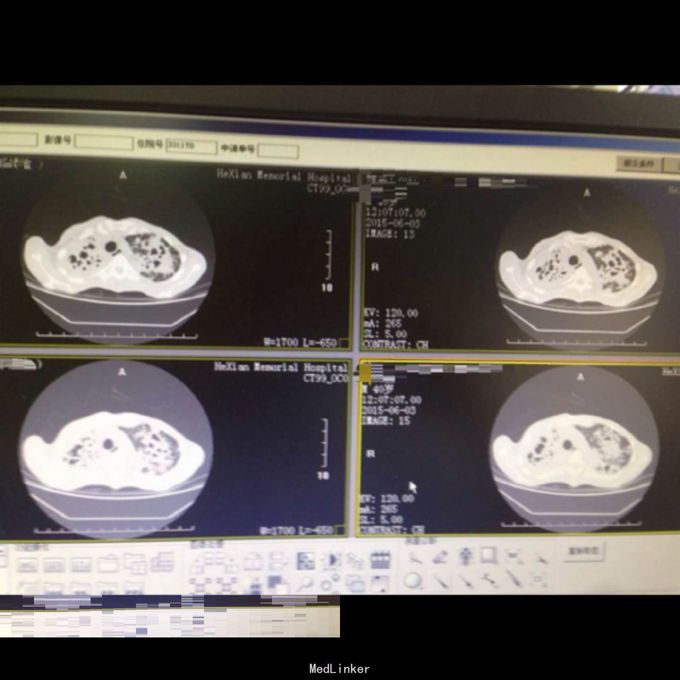

体查:T:36.9℃ R: 23次/分 P:86次/分 BP:130/70mmHg,消瘦,自主体位,神志清楚,对答切题,查体合作。皮肤粘膜未见苍白、黄染,未见皮疹,无皮下出血点,无伤口。全身浅表淋巴结未扪及肿大。口唇红润,伸舌居中,咽部无充血,扁桃体无肿大。颈软,无抵抗,颈静脉无充盈,肝颈静脉回流征(-),气管居中,胸廓对称无畸形、无局部膨隆或凹陷。呼吸平稳,节律规则。双侧呼吸动度对称。双肺部叩诊清音。双肺呼吸音清,双肺未闻及干湿性啰音。心界不大,心率86次/分,律齐,各瓣膜区未闻及病理性杂音。 辅助检查: 双肺CT:1、双肺弥漫性病变,考虑继发型结核,并双肺上叶、下叶背段多发空洞形成、支气管扩张,建议治疗后复查。2、双侧胸膜增厚、粘连,右侧少量胸腔积液。